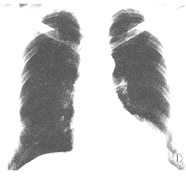

图1 左心尖外缘示有软组织块影与左心缘相连。